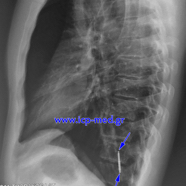

FIG. 3-4:

Preoperative Chest X–rays (posteroanterior and left lateral)